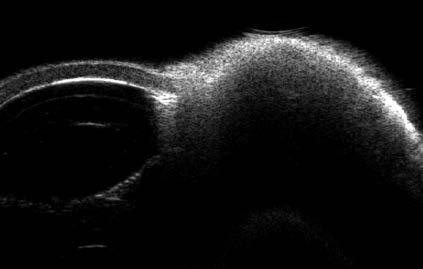

26 ¿Sabe cuál es la prevalencia de quistes en el sulcus ciliar de sus pacientes miopes? Relevancia en implantes fáquicos de cámara posterior

Autor: Dr. Germán R. Bianchi

Sin embargo, hay problemas que pueden evitarse, especialmente en el ámbito de nuestra actividad profesional. Un ejemplo de ello es la presencia de quistes de cuerpo ciliar, cuya existencia puede complicar los resultados en la implantación de lentes intraoculares fáquicos. Tal como explica el doctor Germán Bianchi, estos problemas pueden detectarse y evitarse mediante un examen preoperatorio con UBM.